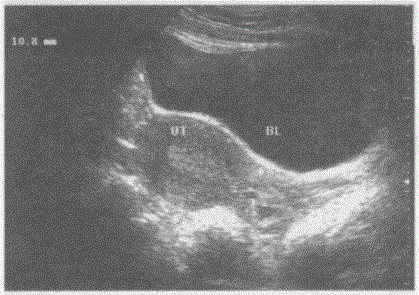

问题 临床资料:女,32岁,常规体检。 超声综合描述:子宫前位,形态大小正常,肌层回声均匀,子宫内膜居中。宫颈部可见数个小无回声区,最大位于宫颈后唇,直径1.0cm,后方声加强。 超声提示:

选项 A.子宫颈正常声像图 B.子宫颈癌合并出血 C.子宫颈积液 D.子宫颈那勃氏囊肿(Nabotlalancysts)

答案 D